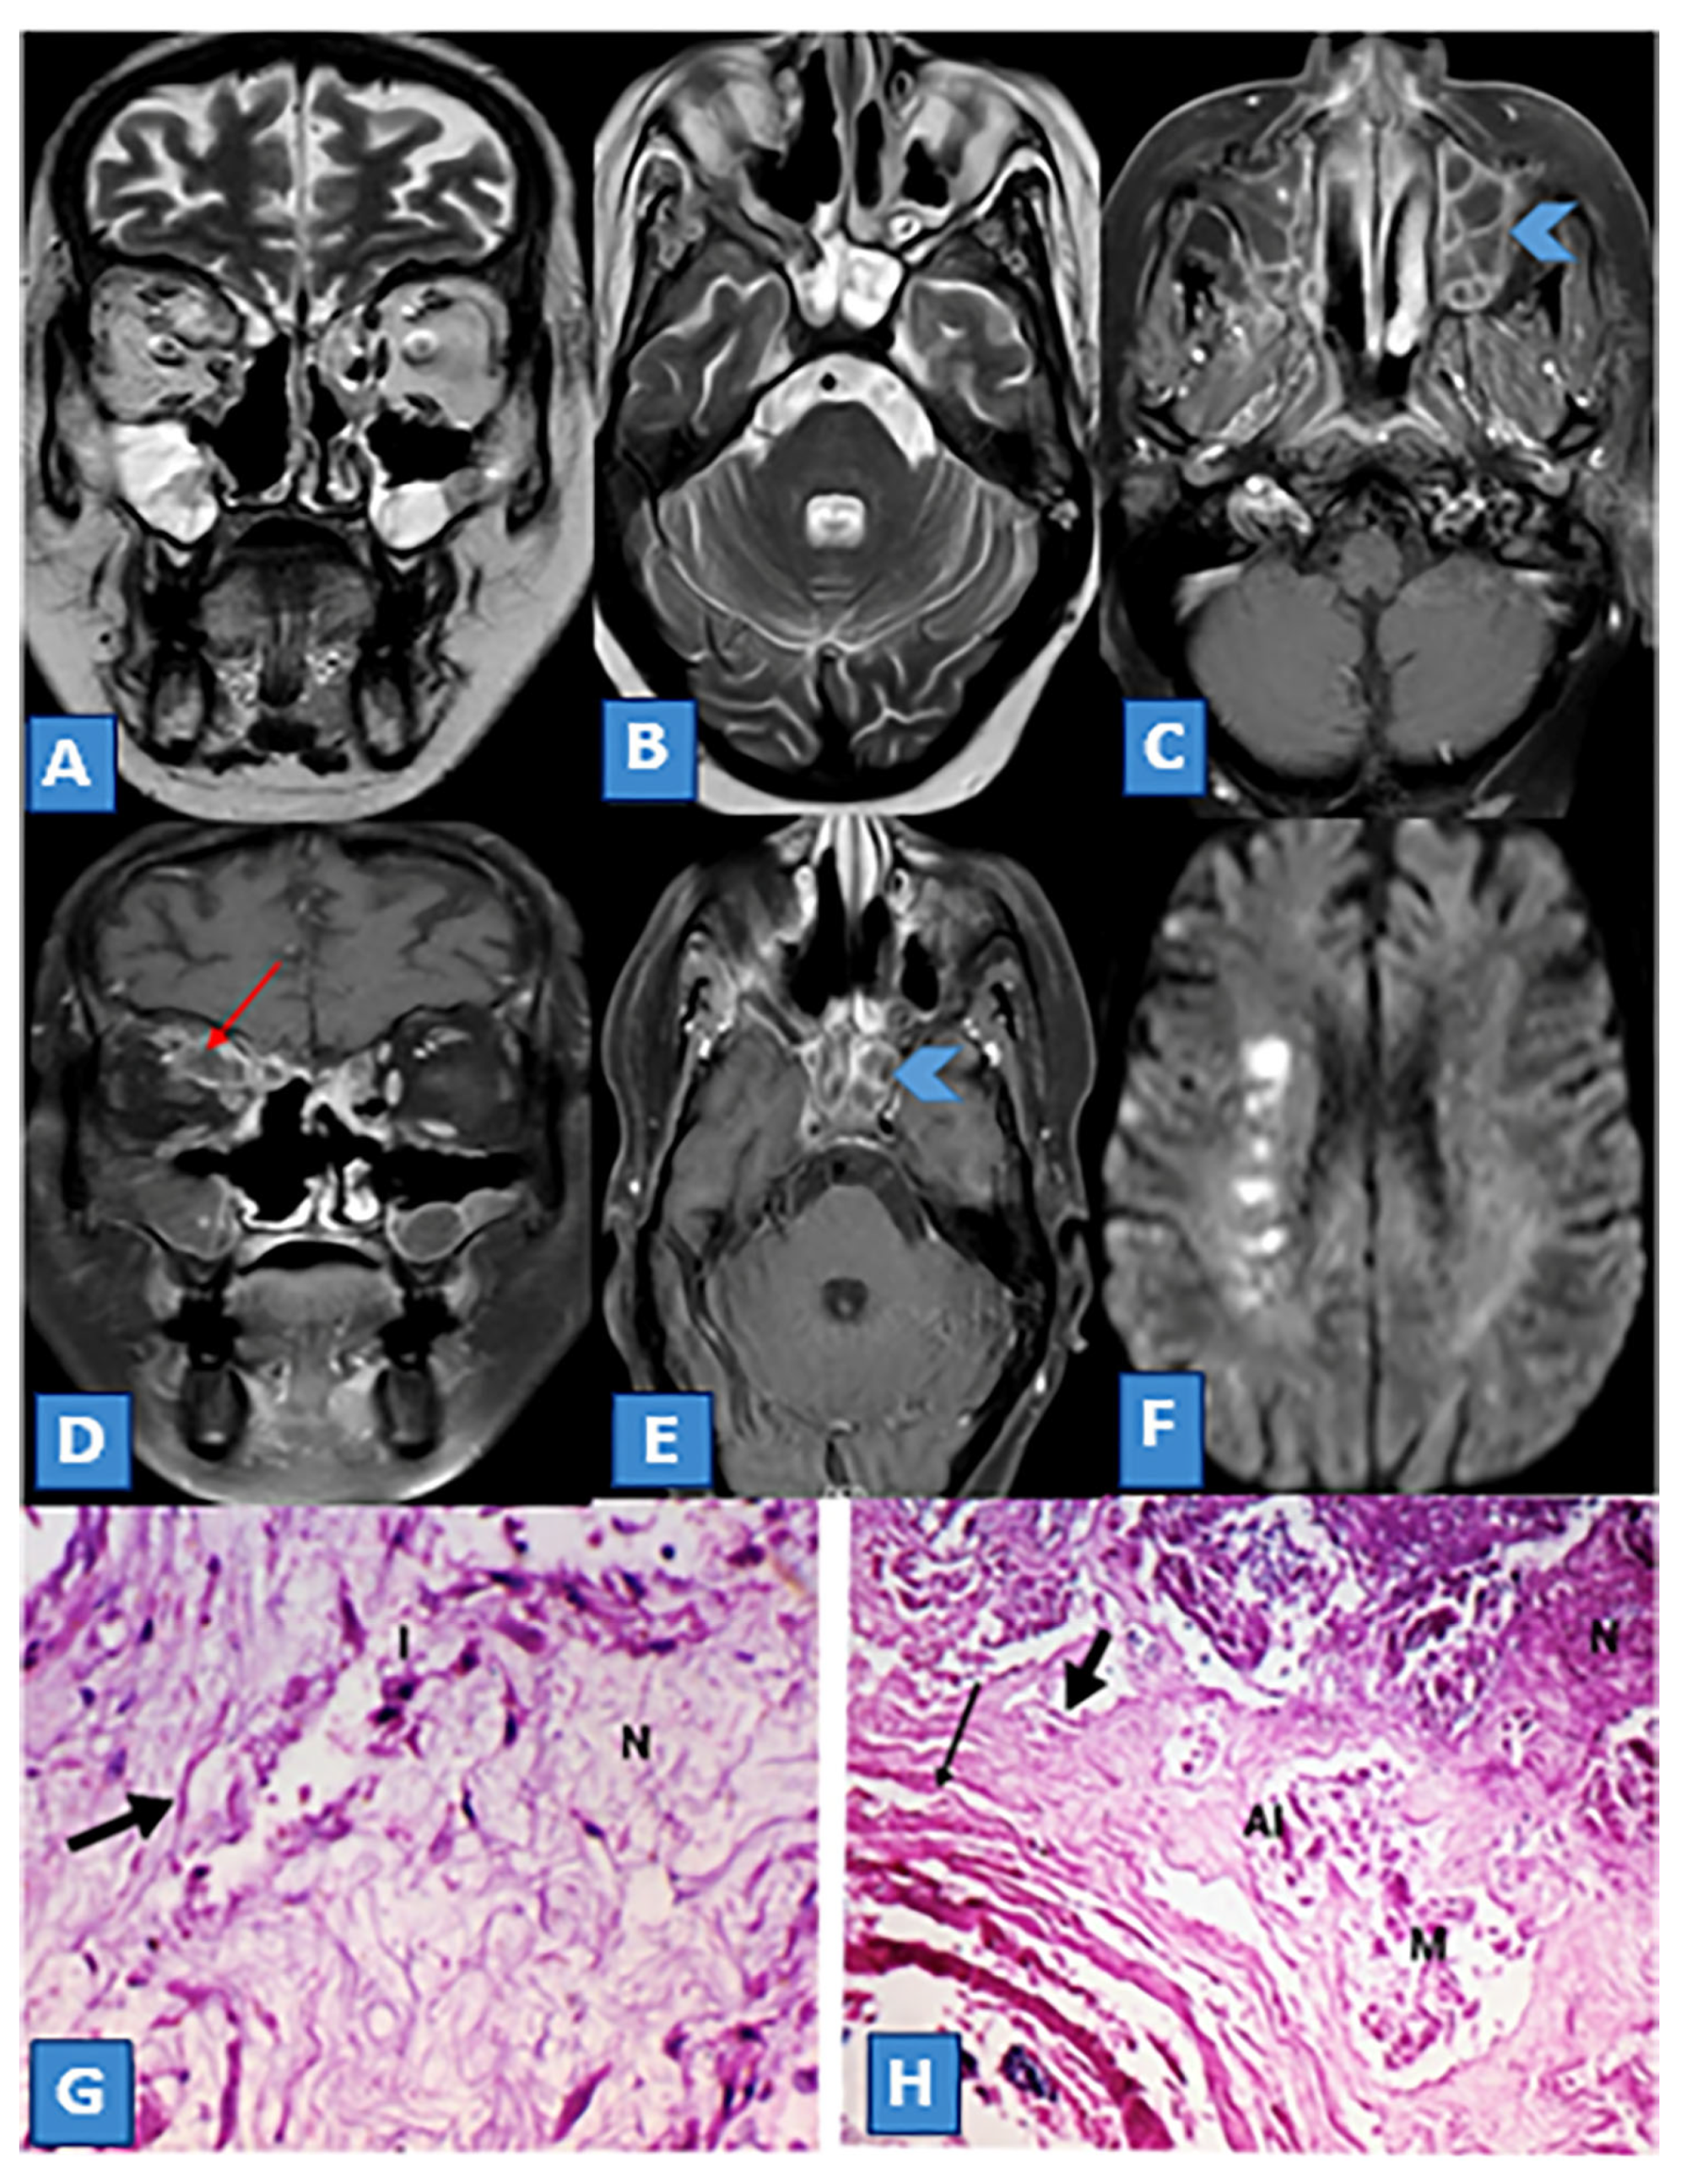

Magnetic Resonance Imaging Features of Rhino-Orbito-Cerebral Mucormycosis in Post-COVID-19 Patients: Radio-Pathological Correlation

3.3. MRI Findings and Signal Characteristics

3.4. Extrasinus Extension

3.5. Histopathological Findings